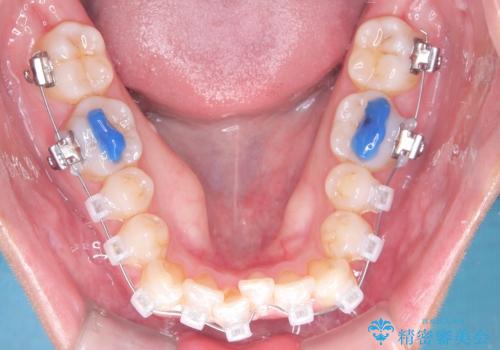

治療計画をしっかり立て、歯の移動量や力のコントロールを最適化することで、約1年という短期間で矯正治療を終了することができました。

「矯正は時間がかかる」というイメージをお持ちの方も多いですが、症例によっては、非抜歯でも短期間で改善が可能な場合があります。

治療後は歯並び・かみ合わせともに大きく改善し、患者様にも大変ご満足いただけました。